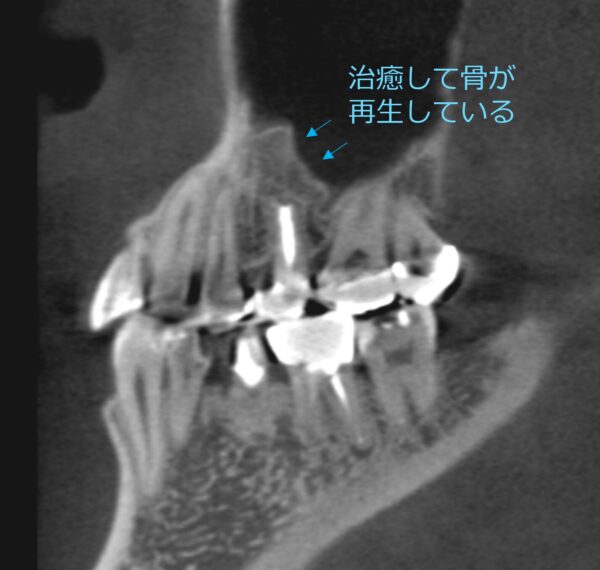

約1年半後のレントゲンでは、炎症によって失われていた骨が再生している様子が確認できました。

歯を抜かずに保存できたことで、患者さまには大変喜んでいただけました。